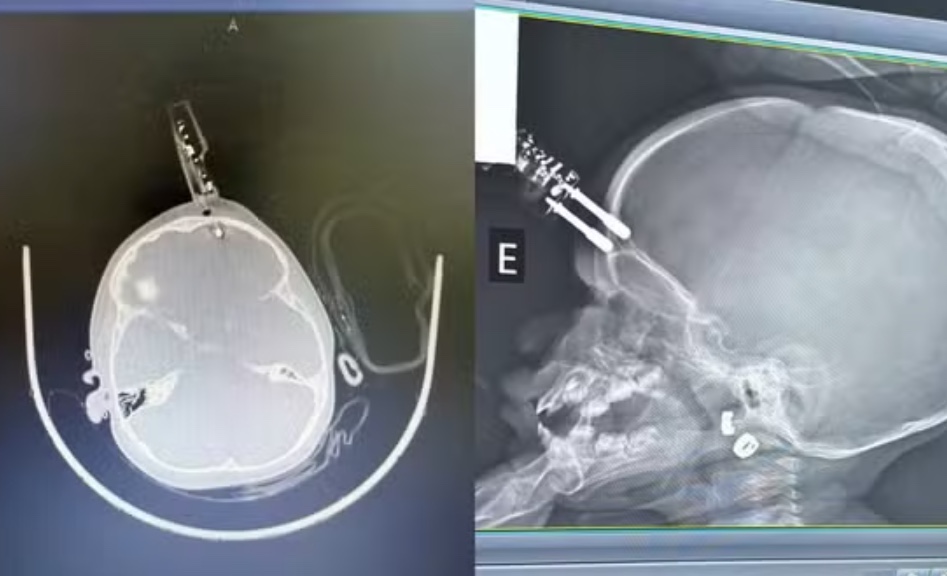

Uma menina de 1 ano ficou gravemente ferida após cair da cama e ter um carregador de celular cravado na testa, em Divinópolis, no Centro-Oeste de Minas Gerais. O acidente doméstico aconteceu enquanto a criança estava sobre o móvel, e o objeto acabou perfurando a região frontal do crânio, muito próxima ao olho, o que exigiu atendimento médico de urgência.

A criança foi levada ao Complexo de Saúde São João de Deus, onde passou por uma cirurgia imediata para a retirada do carregador, limpeza da área atingida e reconstrução do local da lesão. Segundo o neurocirurgião Bruno Castro, o procedimento rápido foi fundamental para evitar complicações graves, como hemorragia cerebral ou infecção, já que o objeto rompeu a barreira natural da pele e poderia permitir a entrada de micro-organismos.